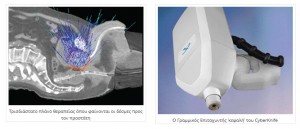

- Ρομποτική Ακτινοχειρουργική με CyberKnife

Διαδικασία για τη θεραπευτική αγωγή με CyberKnife®

Την ημέρα της θεραπείας, προσέρχεται ο ασθενής και ξαπλώνει στο κρεβάτι του συστήματος. Ο τεχνολόγος ακτινοθεραπείας μαζί με τον ιατρό του προσαρμόζουν το αφρώδες στρώμα ακινητοποίησης που έχει φτιαχτεί και με την παρουσία του ακτινοφυσικού ξεκινάει η θεραπεία.

Το CyberKnife® παίρνοντας ειδικές ψηφιακές εικόνες, κάνει έλεγχο της θέσης του ασθενούς και του στόχου και συγκρίνει την παρούσα θέση ασθενούς / στόχου, με την αντίστοιχη θέση που έχει ληφθεί κατά το σχεδιασμό της θεραπείας.

Ο έλεγχος αυτός συνεχίζεται ηλεκτρονικά καθ' όλη τη διάρκεια της θεραπείας. Εάν κάτι μεταβληθεί (π.χ. μετακίνηση του στόχου έστω και δεκάτων του χιλιοστού) λόγω της ύπαρξης των "δεικτών – fiducials" γίνεται αμέσως αντιληπτό από το σύστημα και γίνονται διορθωτικές κινήσεις ώστε η ακρίβεια της στόχευσης να είναι απόλυτη. Ο ρομποτικός βραχίονας κινείται στο χώρο και στέλνει τη δέσμη των ακτίνων που παράγει ο Γραμμικός Επιταχυντής προς το στόχο της θεραπείας με ακρίβεια δεκάτων του χιλιοστού.

Η θεραπεία δεν προξενεί πόνο ή άλλο δυσάρεστο αίσθημα και ο ασθενής χαλαρώνει ακούγοντας απαλή μουσική και βλέποντας το ρομπότ να κινείται γύρω του χωρίς να τον ακουμπάει τίποτε παρά μόνο ακτίνες Χ.

Μετά από 40 έως 60 λεπτά που διαρκεί η θεραπεία, ο ασθενής μπορεί να επιστρέψει σπίτι του και να συνεχίσει τις καθημερινές του δραστηριότητες. Αν η θεραπεία έχει σχεδιαστεί να γίνει σε περισσότερες από μία συνεδρίες, ο ασθενής πρέπει να επανέλθει την επομένη μέρα όπου θα επαναληφθεί η προηγούμενη διαδικασία.

Πλεονεκτήματα CyberKnife®

H Ρομποτική Στερεοτακτική Ακτινοχειρουργική με CyberKnife® αποτελεί όπλο της ακτινοθεραπείας και είναι μια νέα τεχνική με πολλά πλεονεκτήματα σε σχέση με τις υπόλοιπες εναλλακτικές λύσεις που εφαρμόζονται στην αντιμετώπιση του αδενοκαρκινώματος του προστάτη.

Στα παραπάνω έρχεται να προστεθεί και η δυνατότητα παρακολούθησης του όγκου κατά τη διάρκεια της ακτινοβόλησης (real time visualization), διαδικασία η οποία διατηρεί την ακρίβεια της στόχευσης παρά τις μικρές μεταβολές στη θέση του όγκου που προκαλούν οι συσπάσεις του εντέρου.

Προϋπόθεση είναι η τοποθέτηση εντός του προστάτη αδένος, τριών έως τεσσάρων "δεικτών αναφοράς" (3 – 4 fiducials), οι οποίοι εντοπίζονται από το σύστημα κεντροθετήσεως, και ανάλογα με τις μικρομετακινήσεις του στόχου, δίδεται εντολή και ο ρομποτικός βραχίονας διορθώνει την απόκλιση της δέσμης από εκατοστά έως δέκατα του χιλιοστού.

Το ρομποτικής τεχνολογίας μηχάνημα, ακτινοβολεί από εκατοντάδες διαφορετικές γωνίες τον όγκο, δίνοντας μεγαλύτερη ακρίβεια στη στόχευσή του σε σχέση με τις άλλες τεχνικές ακτινοβόλησης και έτσι έχει τη δυνατότητα ασφαλούς χορήγησης της μεγαλύτερης δυνατής δόσης για το καλύτερο δυνατό αποτέλεσμα.

Η κατανομή δόσεως ακτινοβολίας κατά την κλασσική εξωτερική ακτινοθεραπεία. Η μικρότερη του ενός χιλιοστού (< 1 mm) απόκλιση της ευστοχίας κατά την ακτινοβόληση με CyberKnife®, προφυλάσσει τις γειτονικές δομές (όπως το ορθό και την ουροδόχο κύστη) και αυτό σε συνδυασμό με τη δυνατότητα υποκλασματοποίησης (λίγες συνεδρίες – επισκέψεις αλλά αυξημένης εντάσεως – δόσεως κάθε φορά) επιτρέπει ραδιοβιολογικά πολύ ισχυρή δόση ακτινοβολίας στον κακοήθη ιστό χωρίς τις επιπλοκές που παρατηρούνται όταν τα όρια της ακτινοβόλησης ξεφεύγουν προς τους γειτνιάζοντες ιστούς.

Ο τρόπος λειτουργίας του είναι μοναδικός καθώς ο ρομποτικός βραχίονάς του κινείται γύρω από τον ασθενή ακτινοβολώντας τον όγκο από εκατοντάδες διαφορετικές γωνίες, εξετάζοντας ανά κλάσματα δευτερολέπτου τις νέες πληροφορίες που δέχεται από την κάμερα που παρακολουθεί συνεχώς τις ανεπαίσθητες κινήσεις του προστάτη, που γίνονται κατά τη διάρκεια της συσπάσεως του εντέρου και διορθώνοντας αν χρειαστεί τις συντεταγμένες του.

Ο ασθενής ξαπλώνει αναπαυτικά σε έναν ευχάριστο χώρο και αναπνέει κανονικά, δεν περιορίζεται από τίποτα και το μηχάνημα αναλαμβάνει όλες τις παραμέτρους της θεραπείας που θα δοθούν από το επιτελείο των ιατρών και των ακτινοφυσικών.

Κατόπιν είναι η σειρά του σχεδιασμού θεραπείας. Πανίσχυροι ηλεκτρονικοί υπολογιστές, επεξεργάζονται τις ψηφιακές εικόνες των εξετάσεων που έχουν προηγηθεί (αξονική τομογραφία κλπ), και οι εξειδικευμένοι ιατροί και ακτινοφυσικοί, συνεργαζόμενοι εκπονούν το πλάνο – σχέδιο θεραπείας. Το τελικό πλάνο εκφράζει τον καλύτερο δυνατό τρόπο θεραπείας, επικεντρώνοντας εκατοντάδες δέσμες ακτίνων από διάφορες κατευθύνσεις προς το στόχο, ώστε τελικά να επιτύχουμε τη συγκέντρωση της απαιτούμενης δόσης ακτινοβολίας στην περιοχή που πρέπει, αλλά να υπάρχει ασφάλεια και μη κάκωση των παρακείμενων φυσιολογικών ιστών και οργάνων. Επίσης καθορίζεται η δόση ακτινοβολίας που θα δοθεί και ο αριθμός των συνεδριών που θα απαιτηθούν. Αυτό το πλάνο – σχέδιο θεραπείας θα κλιθεί να υλοποιήσει ο ηλεκτρονικός υπολογιστής του ρομποτικού βραχίονα, ο οποίος θα κατευθύνει τις δέσμες του Γραμμικού Επιταχυντή με ακρίβεια μικρότερη του χιλιοστού προς το στόχο.

Τι σημαίνει Ρομποτική Στερεοτακτική Ακτινοχειρουργική με CyberKnife®

Η θεραπεία με αυτό το ρομποτικής τεχνολογίας μηχάνημα ονομάζεται Ρομποτική Στερεοτακτική Ακτινοχειρουργική με CyberKnife®. Ο τίτλος είναι μακροσκελής αλλά πρέπει να συνδυάσει τέσσερις έννοιες:

Ρομποτική:

Όρος που δηλώνει χρήση ρομποτικού βραχίονα. Το CyberKnife® χρησιμοποιεί ρομποτικό βραχίονα με έξι βαθμούς ελευθερίας κινήσεως που του δίνουν τη δυνατότητα προσδιορισμού σημείων στο χώρο με εκπληκτική ακρίβεια (απόκλιση μικρότερη του μισού χιλιοστού) και πιστοποιημένου ειδικά για ιατρική χρήση.

Στερεοτακτική:

Η δυνατότητα προσδιορισμού ενός σημείου στο χώρο, χρησιμοποιώντας Καρτεσιανές συντεταγμένες (τους τρεις άξονες Χ,Ψ, Ζ). Το CyberKnife® έχει αυτή τη δυνατότητα γιατί οι πολύ ισχυροί ηλεκτρονικοί υπολογιστές του χρησιμοποιώντας τα δεδομένα του χώρου από την αξονική και τη μαγνητική τομογραφία, μπορούν να κατευθύνουν το ρομπότ (άρα και τη δέσμη των ακτίνων) με απόλυτη ακρίβεια σε οποιοδήποτε σημείο στο χώρο από διάφορες κατευθύνσεις.

Ακτινο- : Χρήση ακτίνων

Το CyberKnife® χρησιμοποιεί ακτίνες φωτονίων που παράγει ένας υψηλής ενέργειας Γραμμικός Επιταχυντής (ενέργεια έξι εκατομμυρίων Βόλτ – 6 MV) για να σκοτώσει τα καρκινικά και γενικά τα μη φυσιολογικά κύτταρα. Ο Γραμμικός Επιταχυντής του είναι ειδικών προδιαγραφών (μικρών διαστάσεων και "διαστημικής τεχνολογίας") και είναι ανηρτημένος στο ρομποτικό βραχίονα, ο οποίος τον μετακινεί στο χώρο και κατ' επέκταση στέλνει τις ακτίνες στα σημεία που έχουν προσδιοριστεί στο πλάνο θεραπείας.